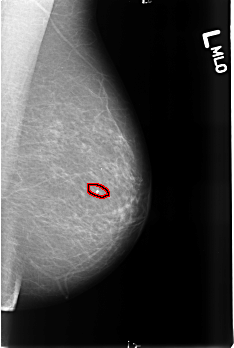

B_3430_1.LEFT_MLO

FILE: B_3430_1.LEFT_MLO.OVERLAY

TOTAL_ABNORMALITIES 1

ABNORMALITY 1

LESION_TYPE CALCIFICATION TYPE COARSE DISTRIBUTION N/A

ASSESSMENT 2

SUBTLETY 5

PATHOLOGY BENIGN_WITHOUT_CALLBACK

TOTAL_OUTLINES 1